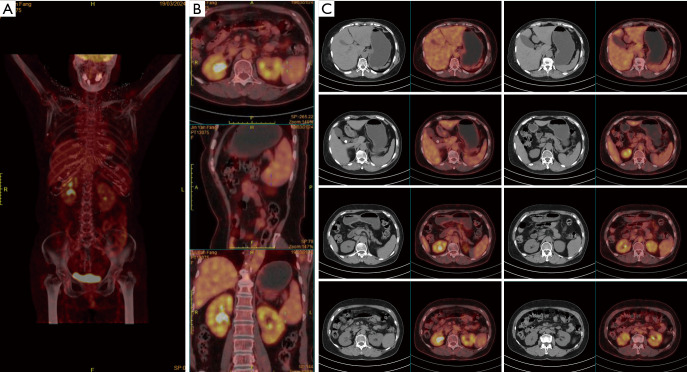

Case description: A 68-year-old female patient presented with abdominal discomfort for over 2 months. Positron emission tomography-computed tomography (PET-CT) examination revealed multiple splenic lesions with no significant abnormalities elsewhere. The patient had a history of rheumatoid arthritis and diabetes. Physical examination showed no significant abnormalities. Blood tests upon admission revealed a platelet count of 39×109 cells/L. An elective laparoscopic splenectomy was performed in April 2024. Postoperative pathology and immunohistochemistry suggested RDD. Based on the lab reports and clinical manifestations, the patient was diagnosed with splenic primary RDD with secondary thrombocytopenia. The patient was followed up regularly, and the platelet level recovered to 222×109 cells/L 1-month post-surgery, confirming the cause of thrombocytopenia as secondary to splenic RDD. No significant abnormalities were found on abdominal CT 5 months post-surgery. Preoperative diagnosis of RDD remains challenging, especially for abdominal primary RDD, as percutaneous biopsy is difficult and imaging studies lack specific features, making the diagnosis still dependent on postoperative pathology and immunohistochemistry.